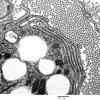

PERIPHERAL NEUROPATHY

4 AXONAL DEGENERATION

4 Macrophages (2)